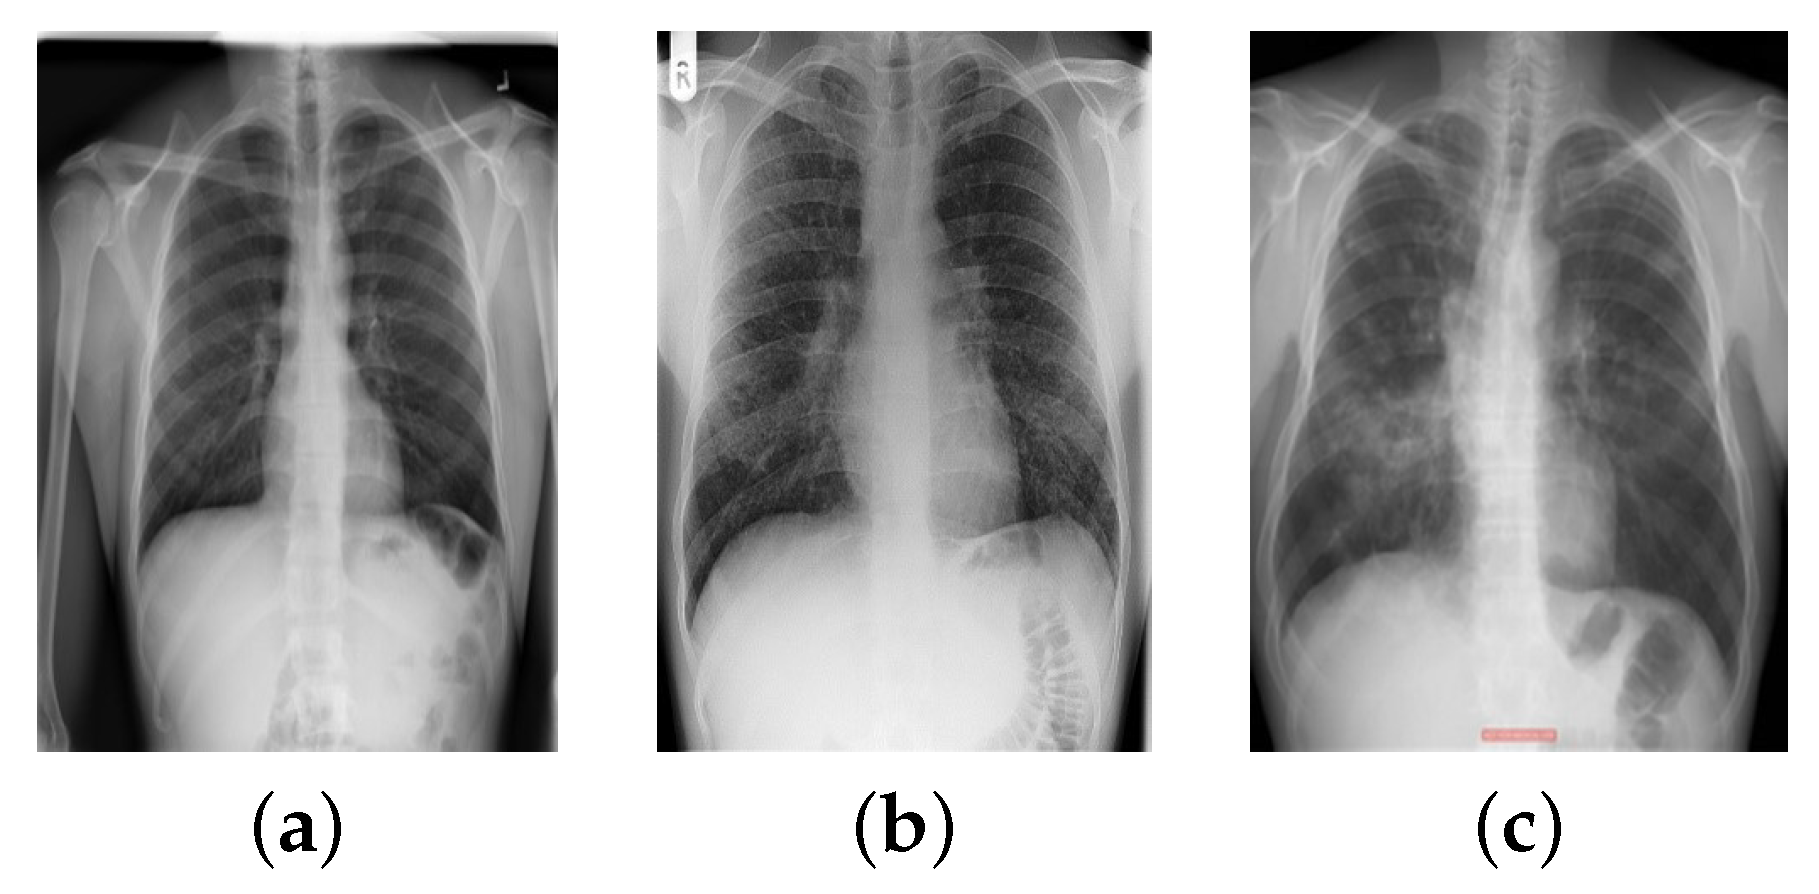

- Image Normalization: Different manufacturers of X-ray devices may provide different-looking X-ray images for the same patient. Overfitting to the device pixel distributions is quite a big problem in computer-aided diagnostic devices; therefore, it is standard practice to apply contrast normalization to minimize this problem. The general idea is to unify the distribution of pixels. This makes X-rays appear a little darker. This procedure generates a view that radiologists would not see in their standard workplace. Using the Reinhard and Macenko approaches, X-ray images were stain-normalized [43,48,49]. A reduction in the color discrepancies of X-ray images improves the classification accuracy of EfficientNet models.